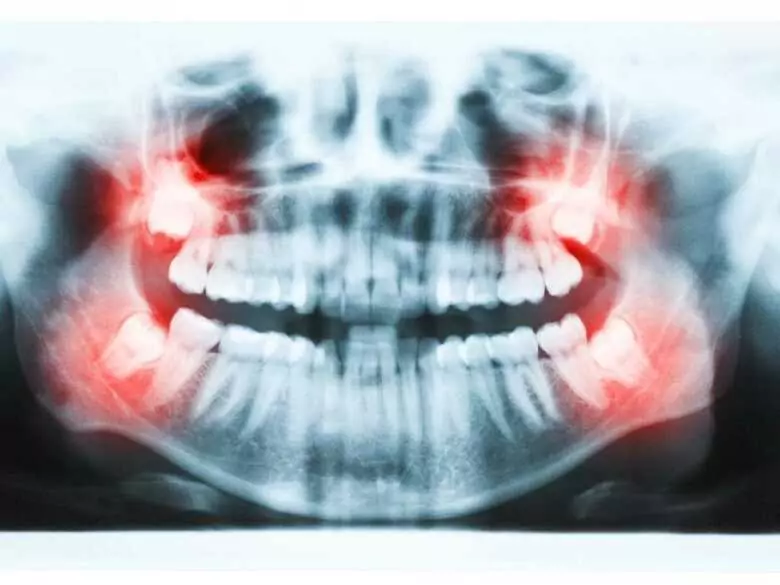

Prześwietlenie zębów

Nowoczesne technologie szybko zmieniają opiekę dentystyczną. W Stanach Zjednoczonych naukowcy testują system, który może przenikać nawet do mniej dostępnych miejsc w jamie ustnej.